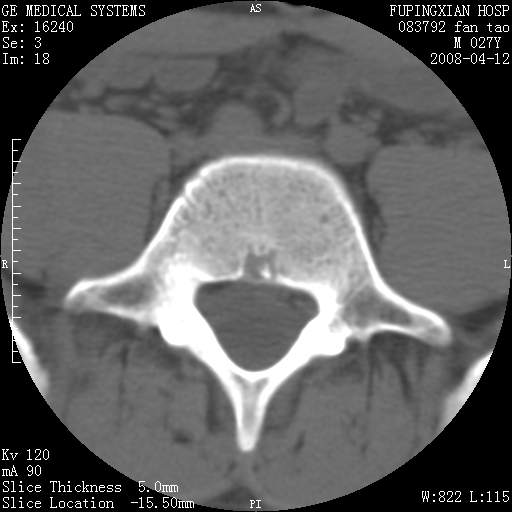

以下是引用前行在2008-4-13 13:53:00的发言:[br]椎间盘髓核终板下突出形成许莫氏结节及椎间盘突出,建议mr检查

以下是引用xclzq_910在2008-4-13 12:43:00的发言:[br]这个应该没什么了,椎间盘突出后反应性骨质吸收硬化.建议mr